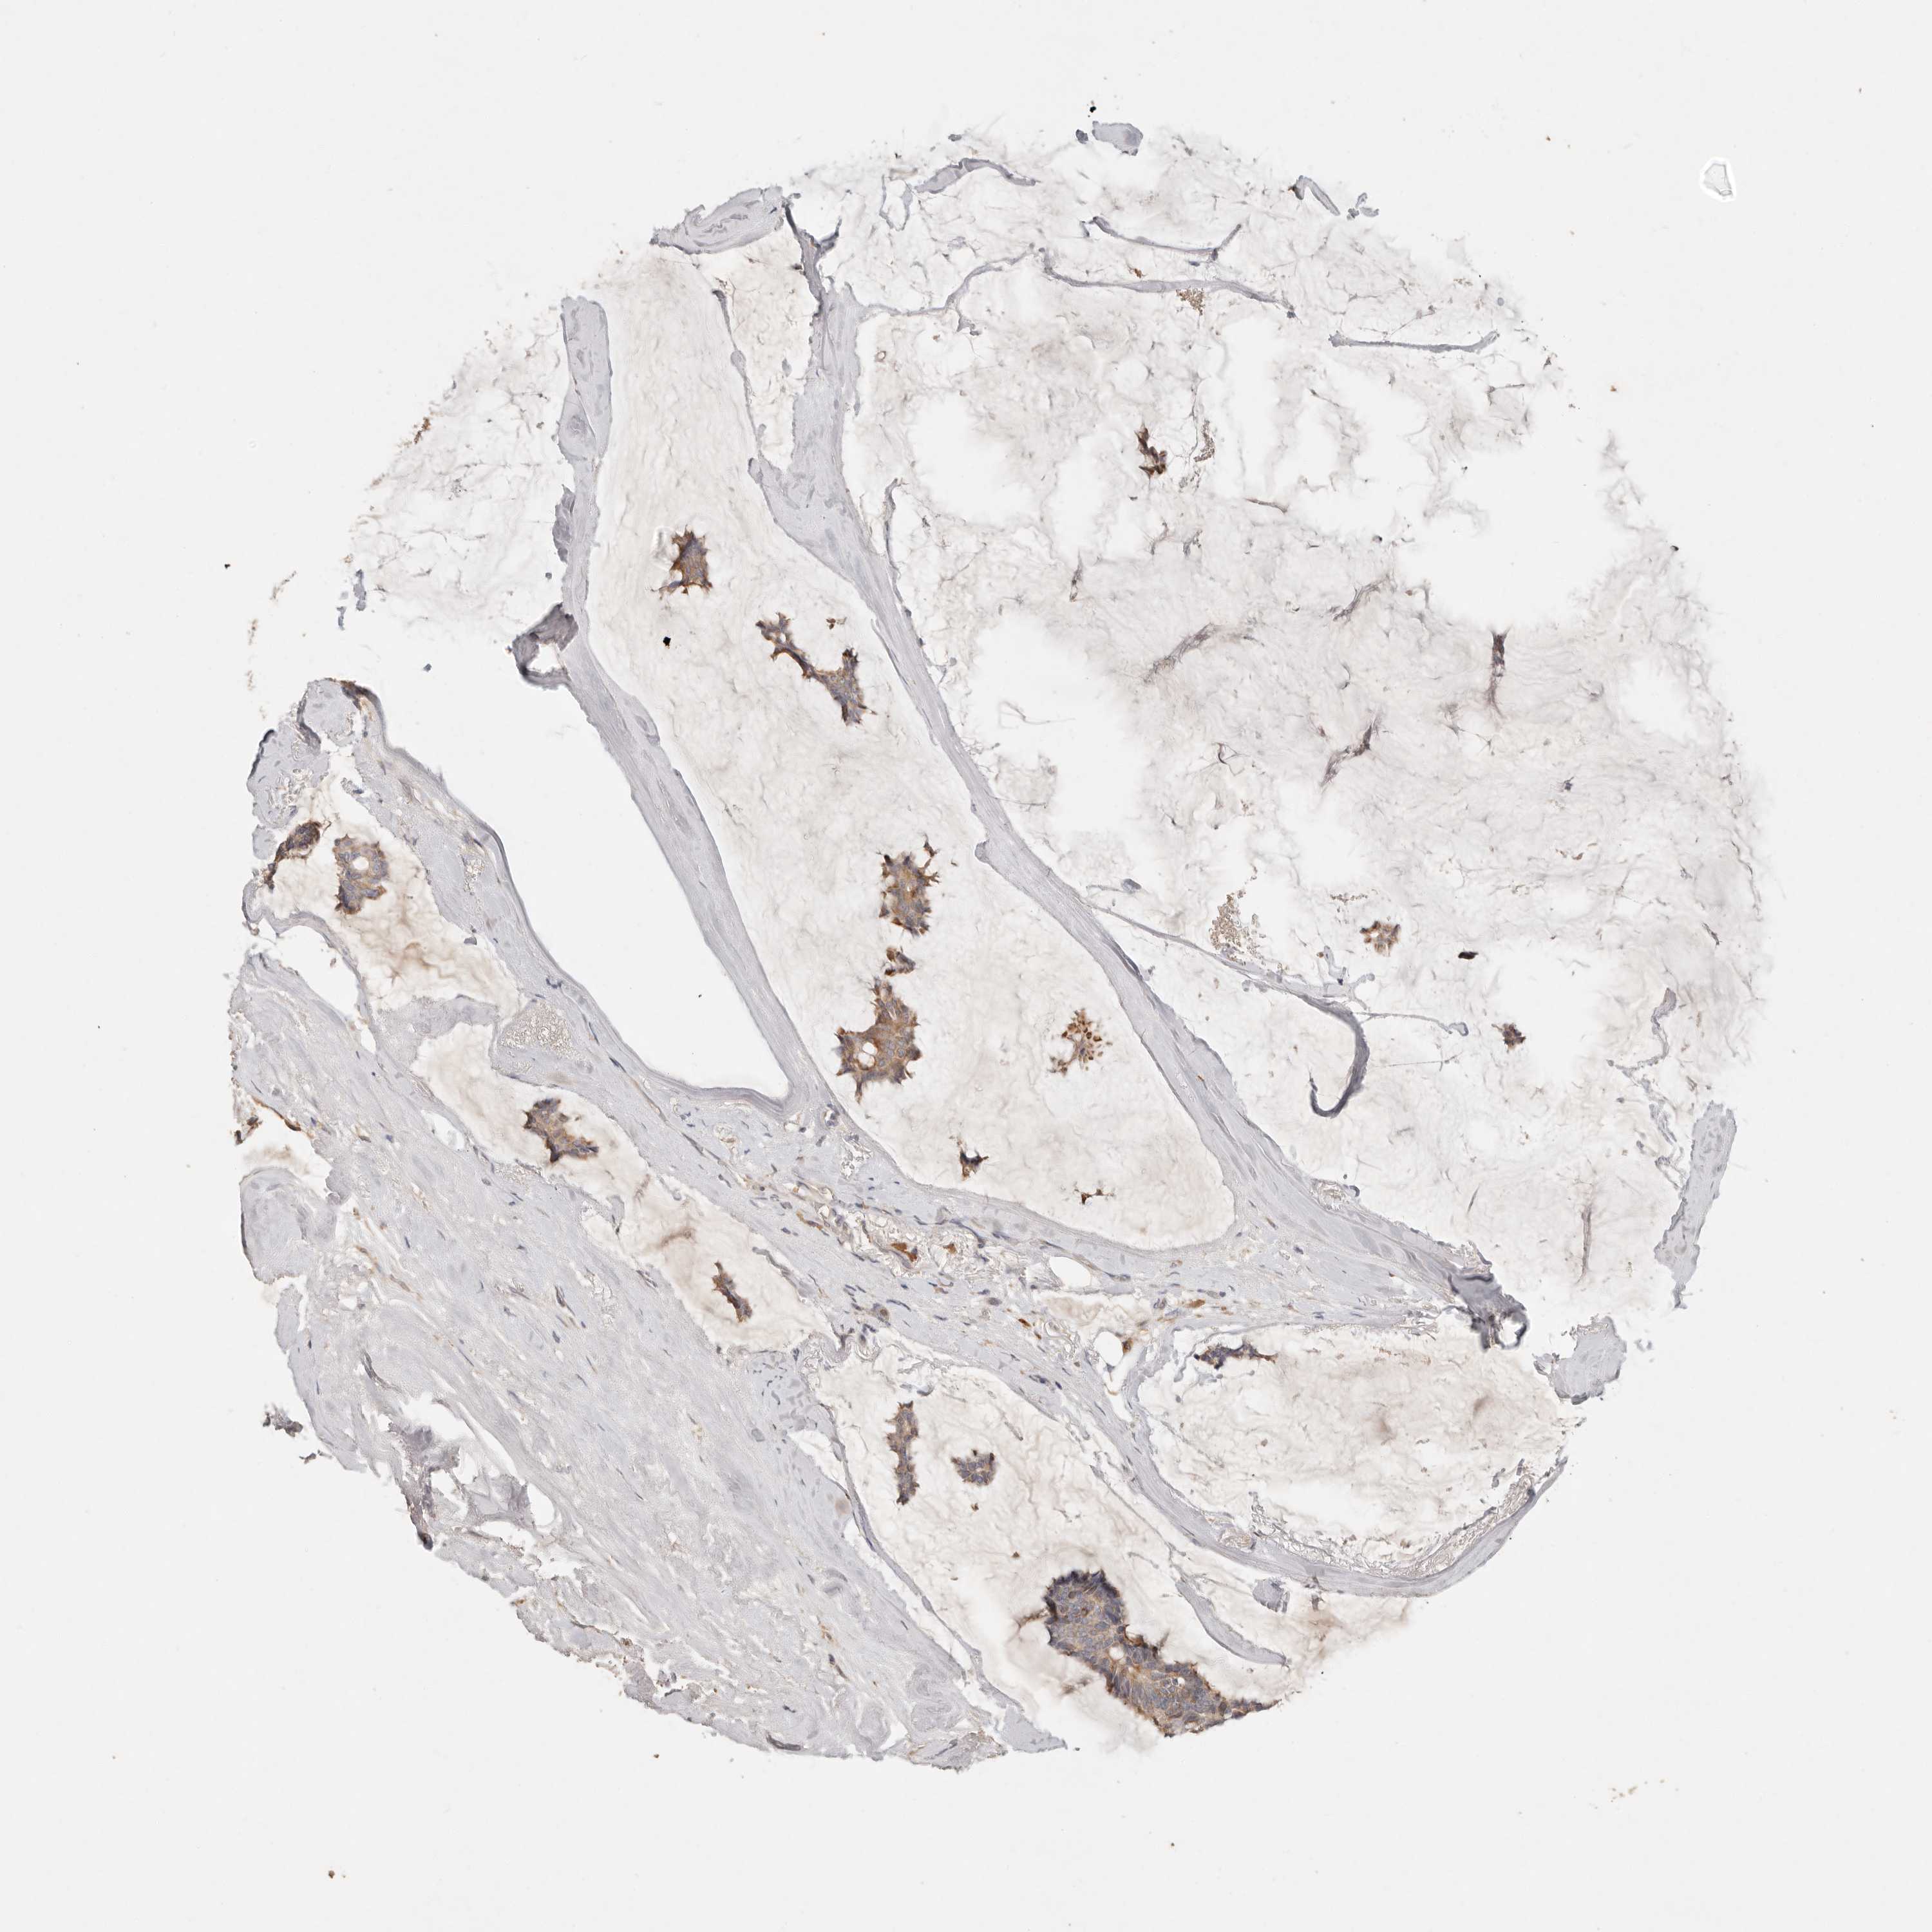

CANCER BREAST CANCER Show tissue menu

BRCA TCGA BRCA VALIDATION PROTEIN EXPRESSION